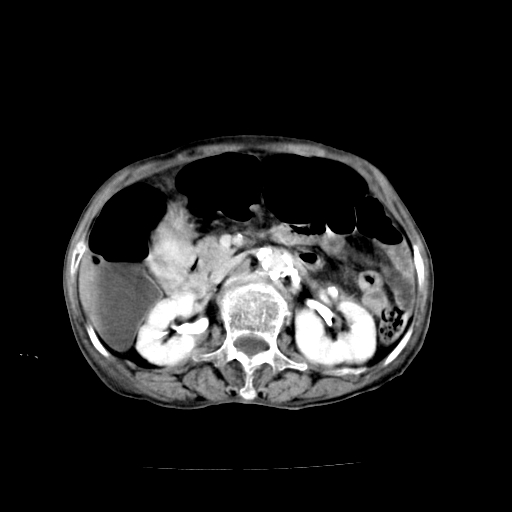

女,68岁,腹胀、恶心两周,先做ct平扫,当时家属不同意强化,6天后家属要求增强扫描。

1、胃窦癌; 2、局灶性脂肪肝。

1、胃窦癌?建议行胃镜!; 2、局灶性脂肪肝。

1)胃窦壁厚,考虑胃窦癌?建议行胃镜检查。 2)局灶性脂肪肝。